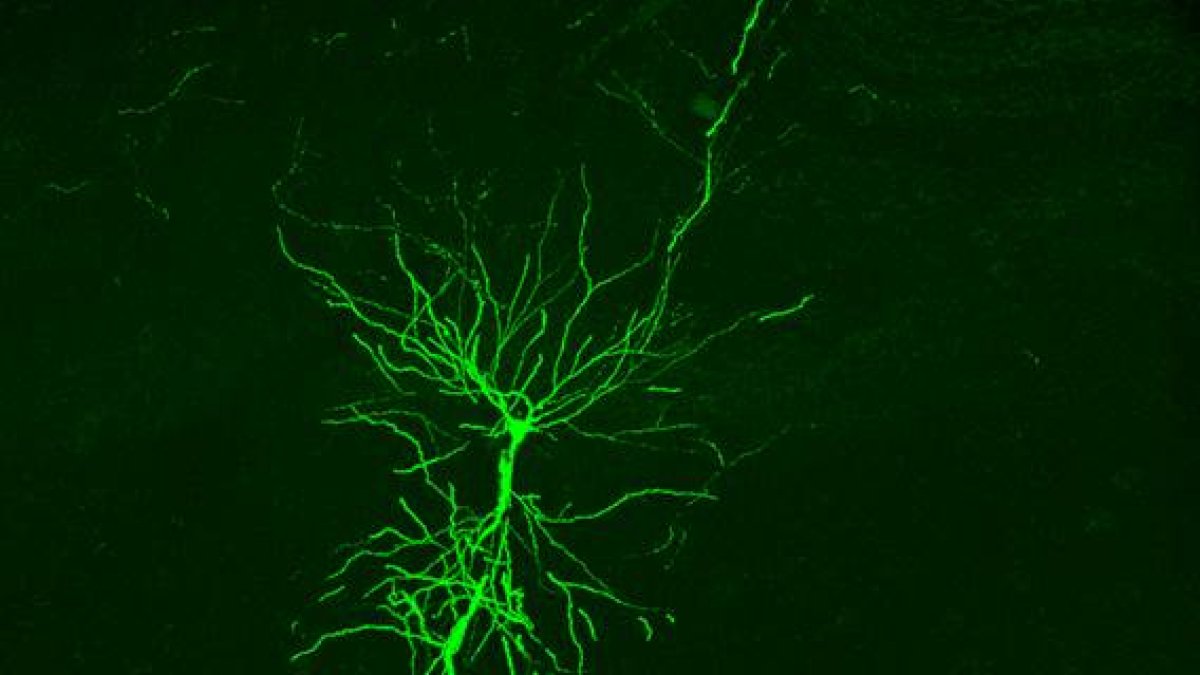

Fotografía cedida por el Instituto Cajal-CSIC de una célula piramidal el hipocampo captada en vivo.